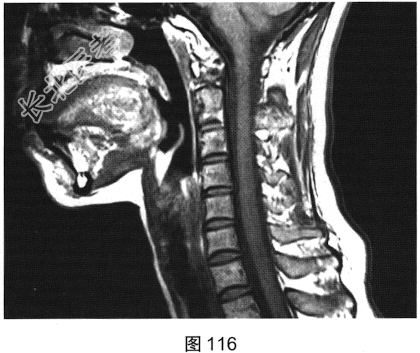

- 多项选择题2.[提示]患者行脊柱MRI检查,如图115~图120所示。患者MRI检查可见哪些阳性影像学表现( )

A、T2WI示颈髓和胸髓病灶呈高信号

B、增强扫描颈髓病灶多发斑片状强化

C、横断面增强扫描脊髓侧索病灶强化

D、T1WI示颈髓病灶呈高信号

E、T2WI示颈髓和胸髓病灶呈低信号

F、T1WI示颈髓病灶呈等信号

G、增强扫描颈髓和胸髓病灶无强化

H、脊髓形态未见异常